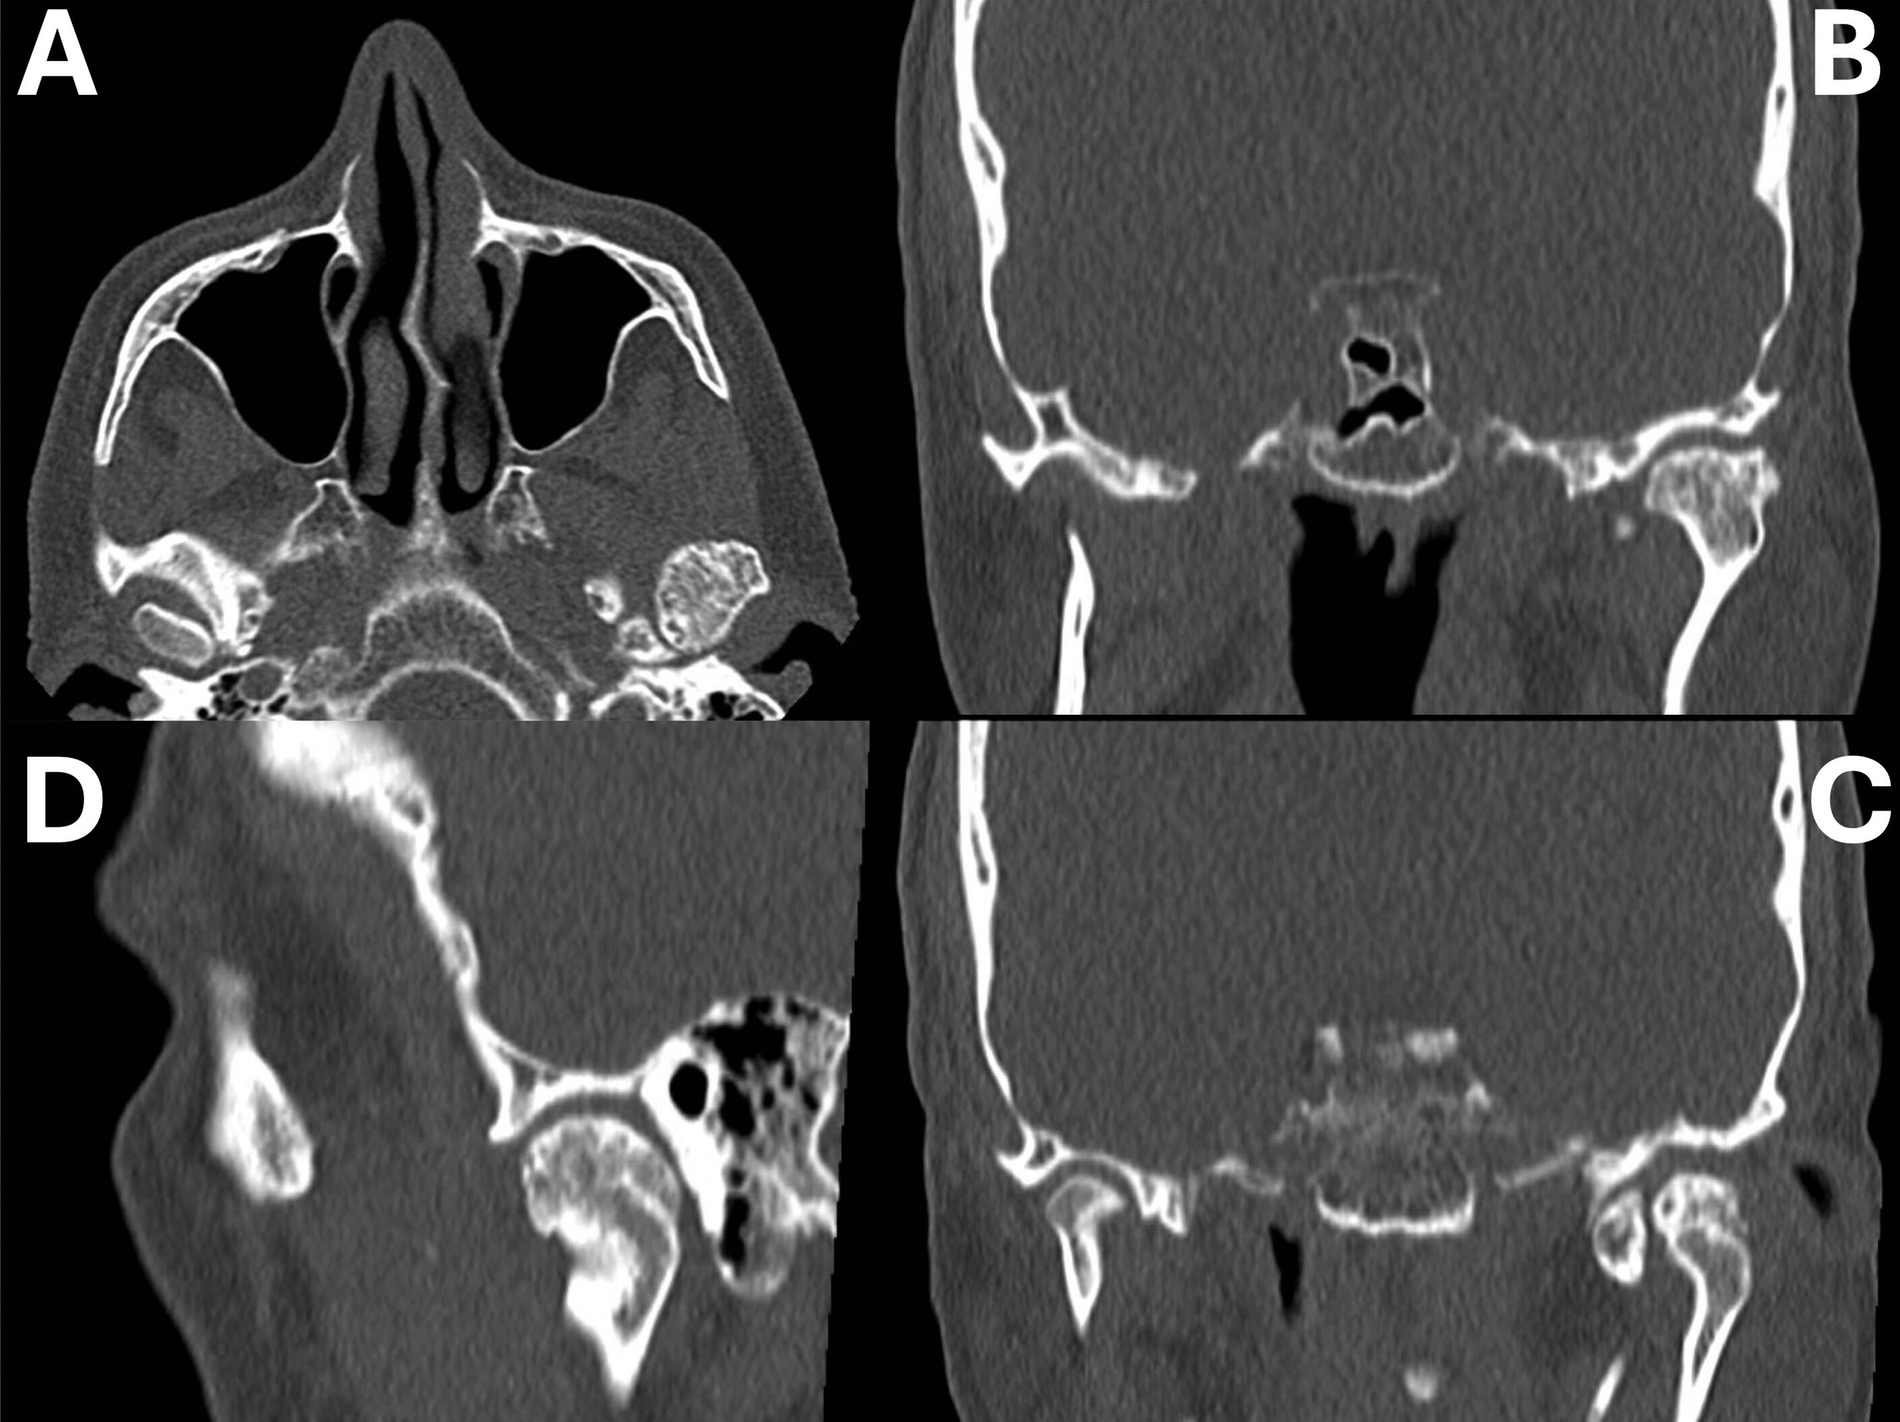

Zur weiteren diagnostischen Abklärung wurde eine digitale Volumentomografie durchgeführt, die eine Ummauerung des Condylus mit knochenähnlicher Hartsubstanz sowie freie, knochendichte Gelenkkörper zeigte (Abbildung 3).

In der zusätzlich durchgeführten Magnetresonanztomografie wurde die Diagnose einer knöchernen, cartilaginär überzogenen Raumforderung des linken Caput mandibulae mit einer Größe von 22 mm x 17 mm x 15 mm gestellt. Zudem waren medial und dorsal 15 mm x 8 mm x 14 mm große Gelenkkörper zu erkennen. Im Hinblick auf diesen Befund wurde seitens der Neuroradiologie die Verdachtsdiagnose eines Osteochondroms gestellt.